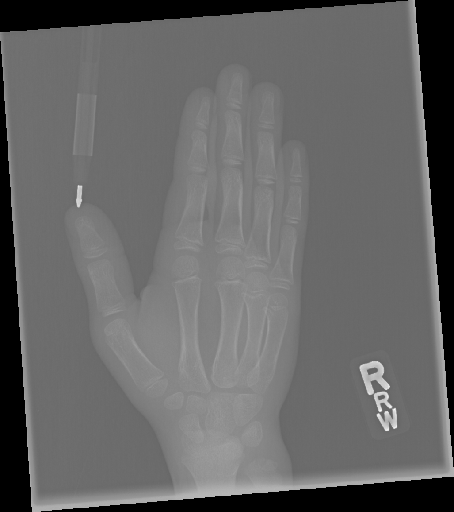

In this work, we focus on a subset of the MURA dataset [17] containing only hand images. In total, we have 5,543 images of 2,018 studies of 1,945 patients. Each study is labeled as negative or positive, where positive means that there was an anomaly diagnosed in this study. There are 521 positive studies, with a total of 1,484 images. Figure 1 shows some examples from the dataset. In summary, our contributions are as follows:

The first step in our pipeline is to detect the X-ray image carrier in the image. To this end, we apply OpenCV’s contour detection using Otsu binarization [14], and retrieve the minimum size bounding box, which does not need to be axis-aligned. This works sufficiently well as long as the majority of the image carrier is within the image (cf. Figure 3). However, the approach might fail for heavily tilted images or those where larger parts of the image carrier reach beyond the image border.

Hand Localization

To further improve the detection of hands, and in particular split the images where two hands are depicted on one image, we manually labeled approximately 150 bounding boxes in the images. Using this small dataset, we fine-tune a pre-trained single shot multibox detector (SSD) [12] with MobileNet as taken from TensorFlow. An exemplary results can be seen in Figure 3.